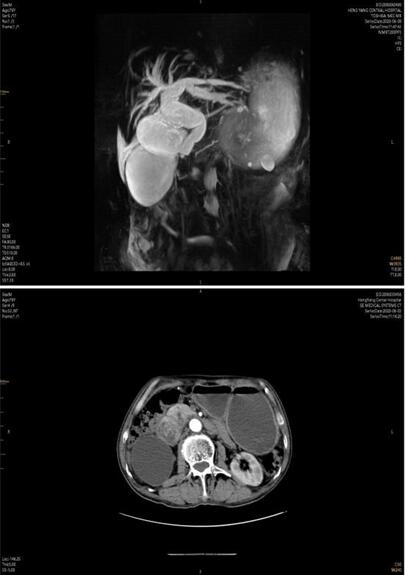

患者家屬經(jīng)多方打聽���,赴我院胃腸外科會(huì)診。譚曙光主任及賀賽奇副主任閱外院腹部CT片��,考慮十二指腸惡性腫瘤合并梗阻可能性大�,唯有手術(shù)治療方為解決患者病癥最好方式?���?紤]患者高齡,全身營養(yǎng)狀況差,脫水及貧血嚴(yán)重���,予積極補(bǔ)液����、維持水電解質(zhì)平衡����、腸外營養(yǎng)支持及輸血治療同時(shí),完善術(shù)前相關(guān)輔助檢查�����。上腹部增強(qiáng)MRI+MRCP檢查提示:十二指腸水平段腫瘤�,侵犯膽管下段、胰頭��、橫結(jié)腸系膜��,并周圍多發(fā)淋巴結(jié)腫大��。十二指腸鏡下活檢病理:十二指腸粘膜慢性炎����。

術(shù)前3天�,患者并發(fā)上消化道出血��,考慮腫瘤病變進(jìn)展�����,侵及十二指腸局部血管出血���,病情緊急��,經(jīng)采取措施積極控制出血及輸血治療后���,譚曙光主任醫(yī)師主持科內(nèi)疑難病例討論:患者為十二指腸腫瘤來源可能性大��,瘤體大���,分期晚�,合并消化道梗阻及出血�,手術(shù)指征明確及迫切。腫瘤侵犯膽管�、胰頭、橫結(jié)腸系膜及血管����,經(jīng)典胰十二指腸切除即Whipple手術(shù)切除困難��,需經(jīng)十二指腸及胰腺后方血管入路(經(jīng)腸系膜上動(dòng)脈及腹主動(dòng)脈��、下腔靜脈表面)進(jìn)行手術(shù)�,難度極大�����,風(fēng)險(xiǎn)極高�,隨時(shí)可能出現(xiàn)大血管破裂大出血并危及生命,為減輕患者創(chuàng)傷����、術(shù)后恢復(fù)快,腹腔鏡手術(shù)操作更是難上加難��。